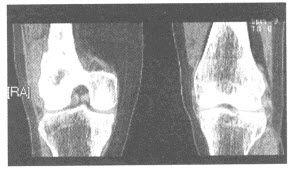

74、单项选择题

患者,女性,50岁,右股骨下端疼痛2个月余,近期加重,右股骨下端外侧触及软组织肿块。膝关节CT图像如下,右股骨下端病变考虑为何种疾病可能性大()

A.软骨肉瘤

B.骨肉瘤

C.骨髓炎

D.骨软骨瘤

E.软骨瘤